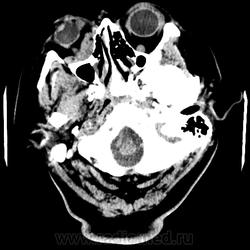

Женщина 48 лет, поступила с подозрением не ОНМК. На КТ -данных за ОНМК не обнаружено, но в правой орбите ретробульбарно мягкотканное образование +45HU, признаков деструкции и ремоделирования костных структур орбиты не наблюдается, медиальная и нижняя прямая мышца отчетливо не дифференцируются, зрительный нерв тесно прилежит к данному образованию. После КУ гомогенное накопление КВ и повышение плотности до +65HU. Экзофтальм. Жалобы на снижение зрения. Год назад делала МРТ ГМ, на снимке патологии орбит не увидел. Идиопатическая псевдоопухоль орбиты?

В мягких тканях носогубного треугольника справа тоже образование.

Контраст